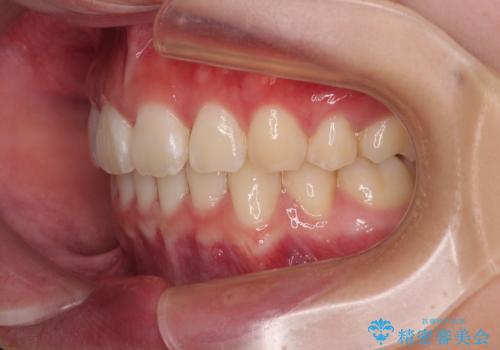

口元が出ているのを改善したい。 クリアブラケットによる抜歯矯正

- 前歯部のデコボコと口元が出ているのが気になるとのことで来院された患者様です。

口元の突出感の解消と、このままデコボコを解消するとさらに出っ歯傾向になってしまうことを考慮し、上下左右の小臼歯を抜歯しクリアブラケットにて矯正していくこととしました。